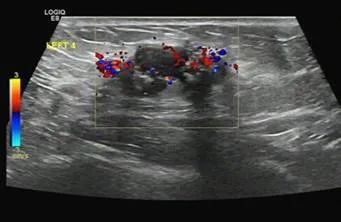

男性,38岁,来院行甲状腺B超检查,超声所见如图

解读:该男性甲状腺B超超声所见结节形态欠规则、纵横比失调,内回声不均,可见多发细点强回声,可见稀疏点状血流信号。恶性结节可能性大,需进一步检查。